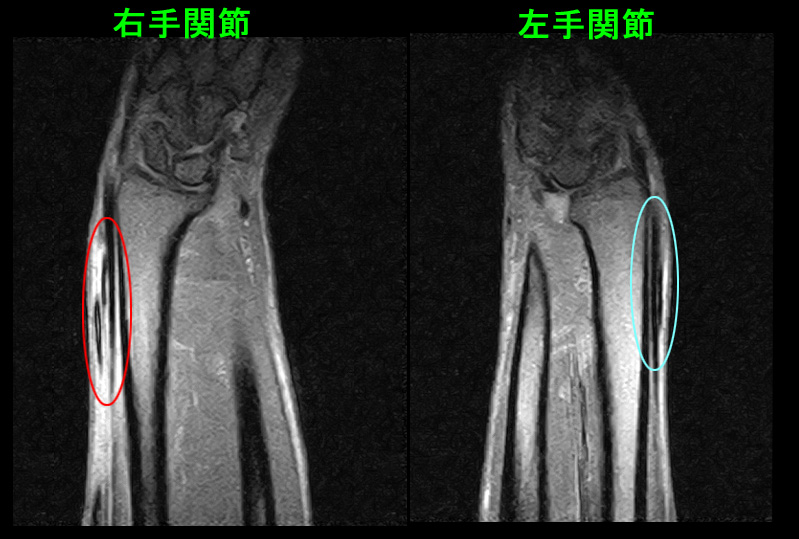

57才男MR1.jpg

MRI所見では前腕遠位(遠位とは体の中心部から遠い位置という意味です)で赤丸領域で黒い腱の周囲が白くなっていて、腱の炎症を示しています。最も皮膚側の黒い腱が母指外転筋腱です。※最初のイラストの腱の構造を参照してください。